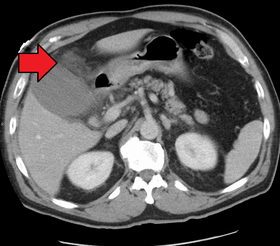

Acute cholecystitis with gallbladder wall thickening, a large gallstone, and a large gallbladder